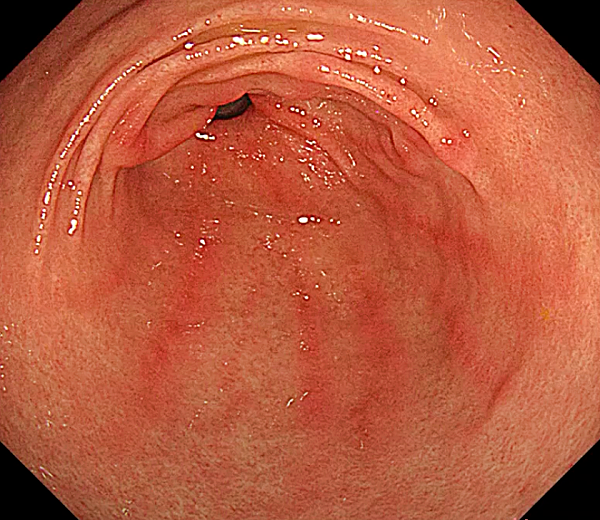

표재성 위염

- 위 점막의 표면에만 염증이 발생하는 가장 흔한 유형의 위염입니다.

- 헬리코박터 파일로리균 감염, 스트레스, 약물, 흡연, 음주 등 다양한 요인으로 인해 발생합니다.

- 속 쓰림, 소화불량, 복통, 메스꺼움 등의 증상이 나타날 수 있습니다.

- 원인에 따라 헬리코박터 파일로리 제균 치료, 위산 분비 억제제, 점막 보호제 등을 사용하여 치료합니다.

- 생활 습관 개선을 통해 증상 완화 및 재발 방지가 가능합니다.